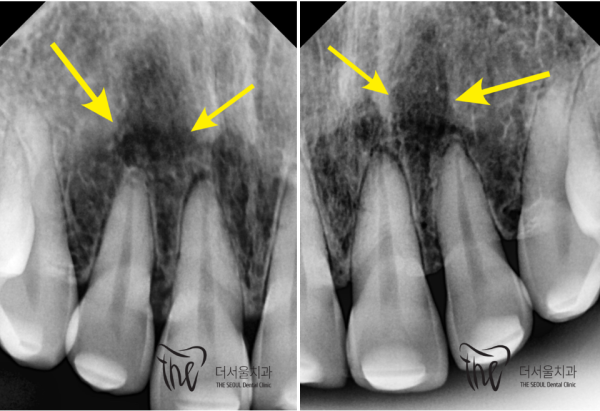

외상으로 인해 충격이 뿌리끝까지 전달되었고

이로인해 염증이 관찰되는 것입니다.

앞니쪽에 통증이 있는 상태였습니다.

이 상태를 그대로 방치하면 치아가 변색되기 때문에

신경치료를 통해 크라운수복까지 해야하는 상황이었습니다.

Trauma sent the shock to the roots

This is why inflammation is observed.

I had pain in my front teeth.

If you leave it as it is, your teeth will be discolored

It was necessary to repair the crown through nerve treatment.